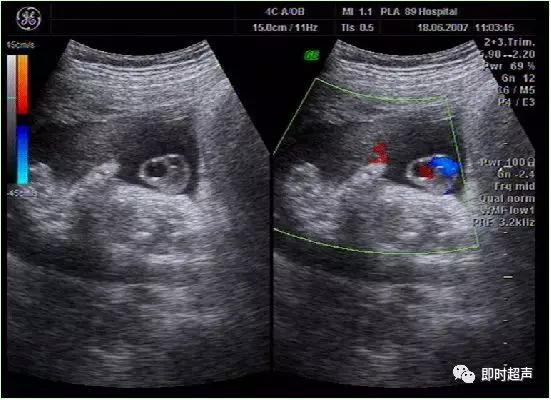

八、单脐动脉(SUA)

正常脐带内有两条脐动脉和一条脐静脉,供给胎儿营养。单脐动脉 , 指脐带内只有一条脐动脉和一条脐静脉,它是最常见的一种脐带异常。发生率约为0. 2% ~1.1%。

单脐动脉超声诊断

单脐动脉胎儿仅见一根脐动脉于膀胱一侧,经膀胱腹部横切面可判断左侧或右侧脐动脉缺如。羊水中脐带纵切面仅见两根血管并行或螺旋状排列, 横切时可见两个大小不一的圆环并行排列,彩色多普勒显示一红一蓝彩色血流信号。